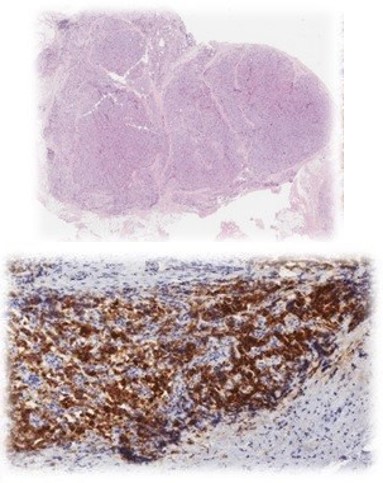

The patient remained disease-free for ten years until new symptoms and biochemical abnormalities reappeared (PTH 229.2 pg/mL, calcium 11.7 mg/dL). Cervical CT and 18F-choline PET-CT identified a hypermetabolic paraesophageal lesion (SUVmax 2.8, 6×7 mm) and three nodules in the upper right thyroid lobe (Figure 1).

Figure 1: (A) Ultrasound: pathological parathyroid gland ultrasound. (B) PET-CT with 18F-Choline: hyperactive parathyroid gland.